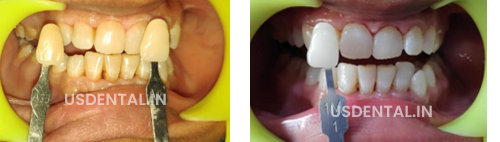

Here, we are sharing shades of the pre- and post- operative pictures of Philips zoom teeth whitening.